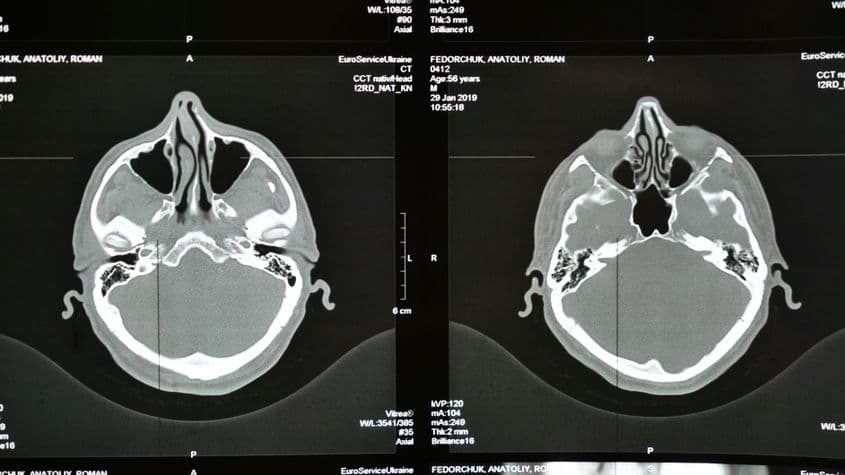

România are cea mai mare rată a mortalității asociată atacurilor cerebrale din regiune. foto: ID 258344974 | Stroke © Travelarium | Dreamstime.com

- În România, accidentul vascular cerebral reprezintă a doua cauză de mortalitate, după bolile cardiovasculare, și principala cauză de dizabilitate, potrivit specialiștilor din cadrul Societății de Neuroradiologie și Radiologie Intervențională din România.

- Un studiu publicat în ianuarie 2023 în European Stroke Journal arată cum România are una dintre cele mai ridicate incidențe de AVC din Europa de Est.

- Același studiu relevă și că România are și cea mai mare rată a mortalității din regiune, 15,74% pentru perioada 2017-2022 analizată de studiu.